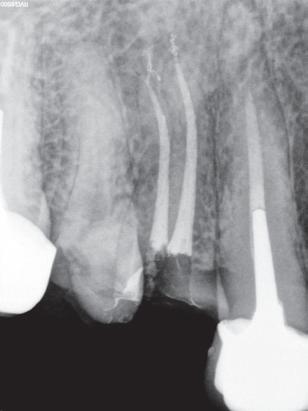

Ny, trådløs endomotor gir maksimal valgfrihet!

Nye Sendoline Endo Motor kan brukes med både roterende og resiprokerende filsystemer!

Stor valgfrihet! Bruk den bare som endomotor, som endomotor med apekslokator eller bare som lokator.

Vinkelstykket har slank, smal hals og et lite hode som kan roteres 360°. Dette gir deg enda bedre og enklere tilgjengelighet i munnen, med optimal sikt.

Rotary S5 System

Reciprocating S1 System

16.990,-